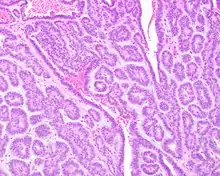

Canalicular adenoma growths are usually small at the time they are noticed, with an average size of about 1.6 cm.[1] Their histologic appearance is very distinct, with a channel-like pattern between cords and ribbons; the pattern has been described as resembling a "string of pearls."

A hematoxylin and eosin stained slide of canalicular adenoma showing large canaliculi

A hematoxylin and eosin stained slide of canalicular adenoma showing beading

The growths often contain are often small bight squamous balls, or morules. They also tyipcally contain a well-developed supporting tissue - a fibrous stroma - which is rich in hyaluronic acid and chondroitin sulphate.[1] In a few cases, the growths may contain small calcium deposits or microliths. Although it is seldom necessary, a pathologist can confirm the existence of canalicular adenoma through immunohistochemistry studies, with the cells reacting with pancytokeratin, S100 protein and SOX10, with a delicate GFAP reaction around the periphery.[5][1][6][7] Although it is a benign tumor, a positive diagnosis of canalicular adenoma may be necessary to exclude the existence of other medical conditions such as a basal cell adenoma, pleomorphic adenoma, adenoid cystic carcinoma, and polymorphous adenocarcinoma.